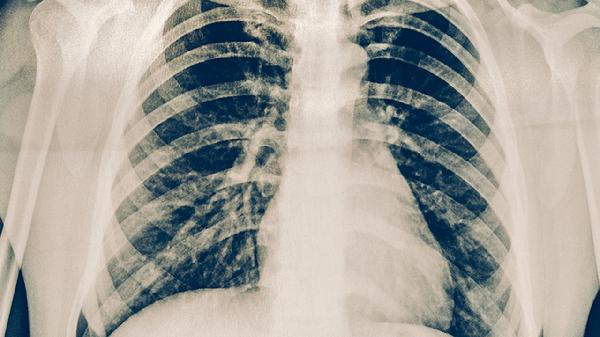

胸部X線檢查可發(fā)現(xiàn)肺結(jié)核的典型表現(xiàn)如上肺野浸潤(rùn)影、空洞形成等。該檢查具有輻射量小、費(fèi)用低的優(yōu)勢(shì),適合作為初篩手段。但部分早期病變或特殊類型肺結(jié)核可能表現(xiàn)不典型,需結(jié)合其他檢查綜合判斷。